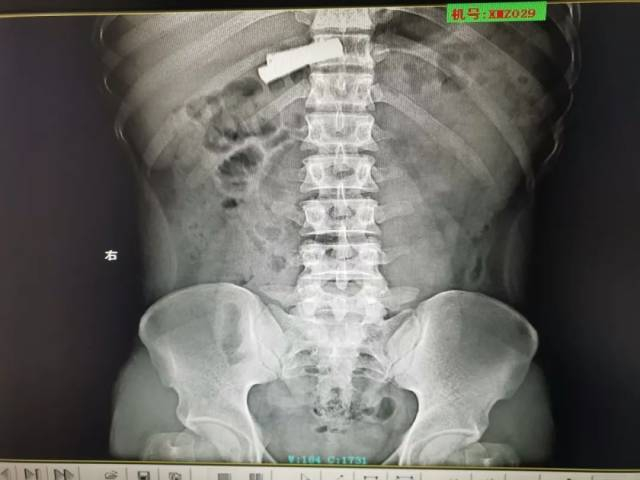

X光下看到电池正处于胃腔

根据X光片进行判断后,孙先生的确吞食了两节电池,万幸的是电池尚未进入小肠。但距离吞食电池已经过去了三个小时,电池随时有可能发生漏液情况,如果发生漏液情况,电池释出的腐蚀性物质不仅会使胃肠道溃烂,还可能引起中毒,甚至会导致严重出血。